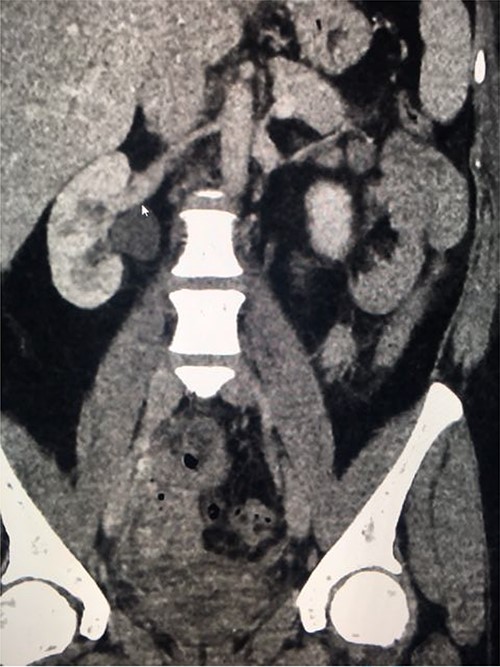

Computed tomography (CT) with urographic phase imaging demonstrated a right distal ureteric injury with leakage of urine into the pelvis and fistulation into the vagina (Figs 1 and 2). A diverting right percutaneous nephrostomy was inserted in the interventional radiology (IR) suite. An antegrade ureterogram at the same time demonstrated a complete discontinuation of the ureter which appeared retracted (Fig. 3).

Coronal nephrogenic phase CT urogram showing hydronephrosis of the right renal pelvis.